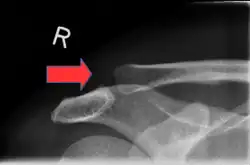

Schultereckgelenksprengung links: Tiefstand der linken Schulter mit Hervortreten des Schlüsselbeinendes („Klaviertastenphänomen“).

Es kann sich neben dem Unfallhergang entsprechenden Verletzungen der Haut (Abschürfungen, Hämatom) eine Vorwölbung im Bereich des Gelenks sowie ein Höherstand der Klavikula bereits bei Ruptur des Lig. acromioclaviculare präsentieren. Bei einer kompletten Ruptur (Tossy 3) und angedeutet auch bei größeren Teilrupturen kann bei der körperlichen Untersuchung das meist schmerzhafte „Klaviertastenphänomen“ ausgelöst werden: das nach oben abweichende äußere Ende des Schlüsselbeines kann vom Untersucher wie eine Klaviertaste nach unten gedrückt werden, federt aber beim Nachlassen des Druckes sofort wieder nach oben. Das Ausmaß des Klaviertastenphänomens ist ein indirekter Hinweis auf das Ausmaß der Bandverletzung.